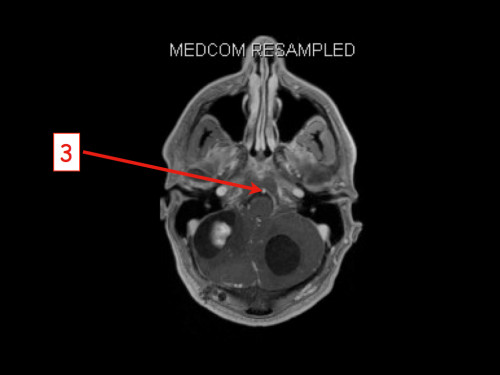

3. Schwindel und Kopfschmerzen, 3 Jahre nach Phäochromozytom-Resektion

Schwindel und Kopfschmerzen, 3 Jahre nach Phäochromozytom-Resektion

19-jähriger Mann. Er klagt seit mehreren Wochen über Schwindel und Kopfschmerzen. Im Alter von 16 Jahren sind er und sein Zwillingsbruder an einem Phäochromozytom operiert worden.